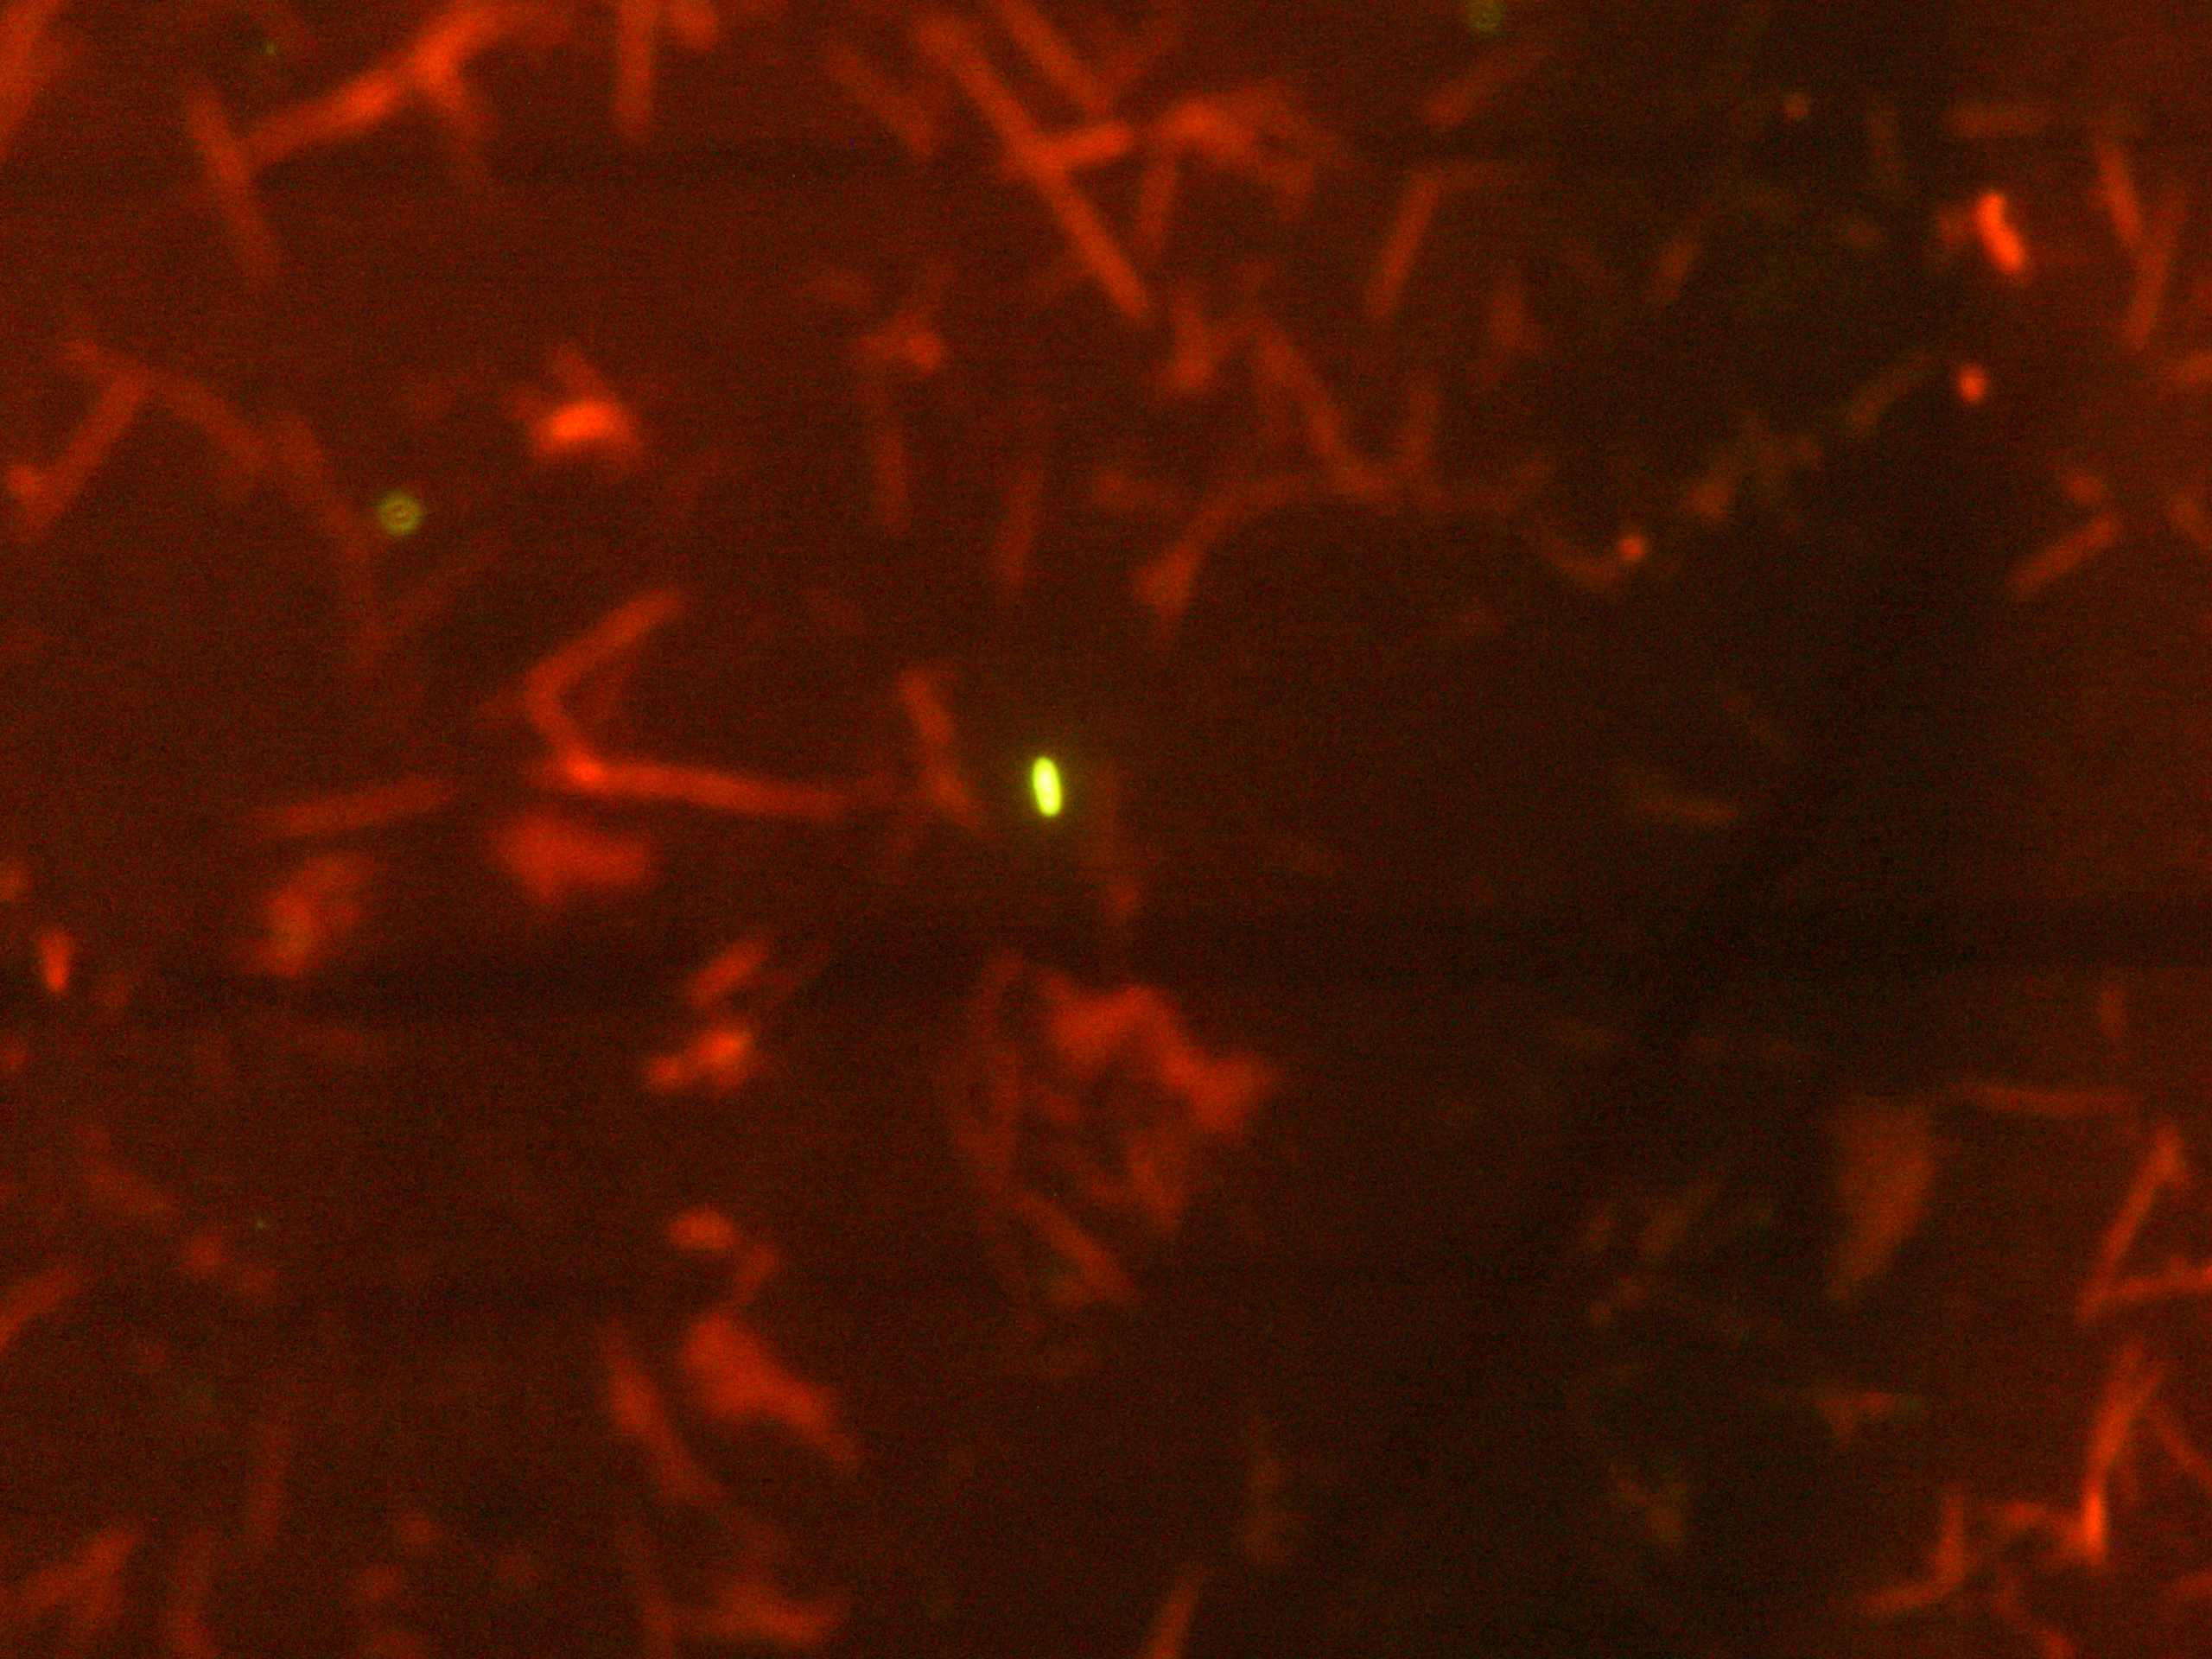

Un equipo liderado por investigadores del Consejo Superior de Investigaciones Científicas (CSIC) ha descrito y caracterizado la microbiota presente en la vesícula biliar humana, un ecosistema de microorganismos poco estudiado hasta ahora. Los investigadores, que publican sus conclusiones en la revista Microbiome, han detectado por primera vez la presencia de distintas comunidades microbianas en la bilis de personas sin ninguna patología hepatobiliar.

Los científicos han empleado técnicas de secuenciación masiva para ahondar y poner de manifiesto la existencia de bacterias pertenecientes a cuatro filos diferentes, principalmente Firmicutes, Bacteroidetes, Actinobacteria y Protebacteria.